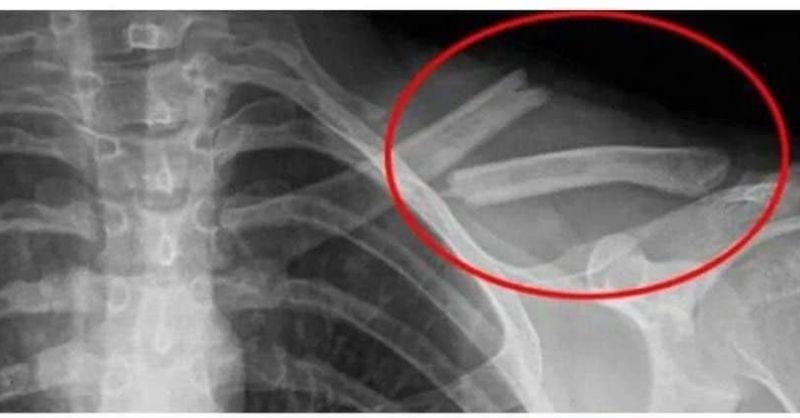

Eating these foods will reduce the amounts of calcium in the body, causing negative effects on bones and joints

Eating these foods regularly will cause calcium in the body to decrease, causing negative effects on bones and joints. 1. Salty Foods Delicacies such as pickles, ham, instant...